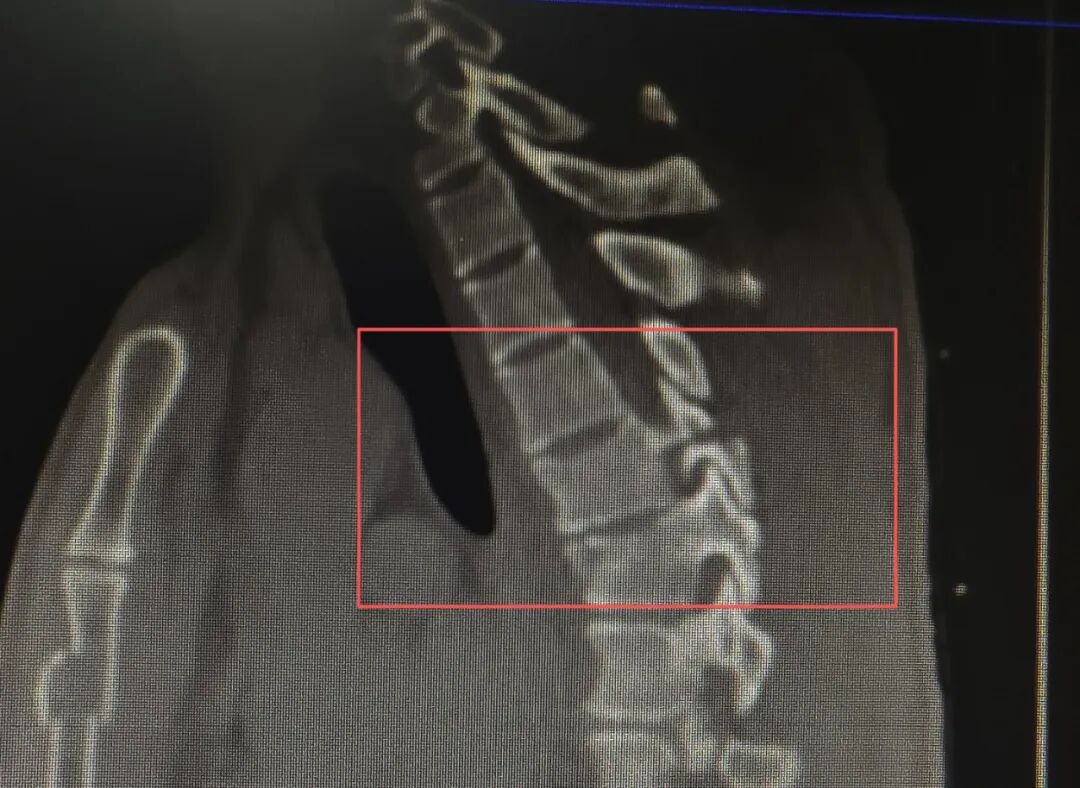

辅助检查进一步明确病情:CT 影像清晰显示患者胸椎多发骨折,胸 5、6 椎体水平椎管受累,骨折块突进椎管内部,直接压迫脊髓,这正是导致患者双下肢活动障碍与小便潴留的核心原因;核磁共振检查同样印证了胸 5、6 椎体对应椎管的受累情况,为后续治疗方案制定提供了精准依据。